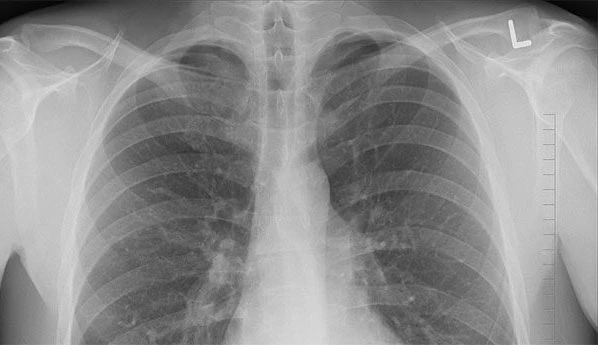

7. Cách phổ biến nhất để chẩn đoán bệnh lao là chụp X-quang ngực nhưng cũng có thể làm xét nghiệm máu. Ảnh: CDC.